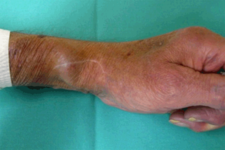

Patienten die sich einer regelmäßigen Blutwäsche unterziehen müssen (Dialyse), haben dafür einen operativ geschaffenen Gefäßzugang zum Punktieren (Dialysefistel/Dialyseshunt). Dazu wird eine Hautvene direkt an eine Arterie angeschlossen. In dieser Shuntvene können Einengungen und Verschlüsse auftreten, die mit vielen interventionellen Methoden behandelbar sind. Diese Behandlungen führen wir über einen Zugang in der Shuntvene meist ambulant in Zusammenarbeit mit der jeweiligen Dialyseeinrichtung durch.